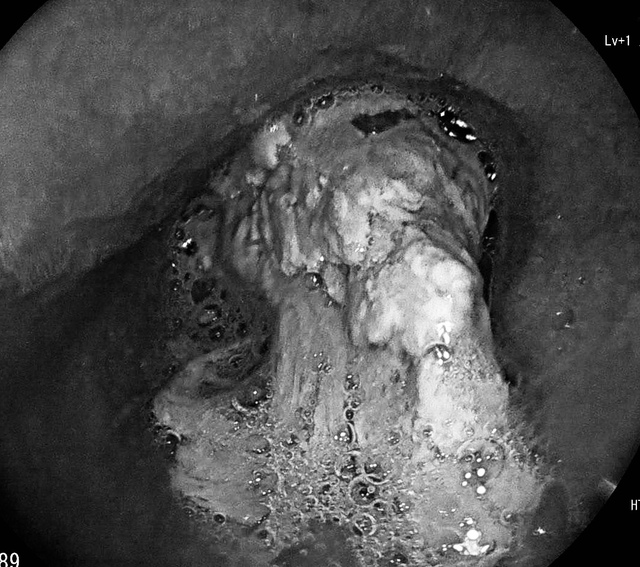

Trước đó, ông Đ.N.C. (SN 1964, trú tại xã Ninh Châu) đến viện trong tình trạng nuốt nghẹn sau bữa ăn. Bệnh nhân cho biết bản thân có tiền sử hẹp thực quản. Kết quả nội soi thực quản – dạ dày ghi nhận khối thịt lớn bít gần kín thực quản ông C.

Khối thịt lớn bít gần kín thực quản bệnh nhân cao tuổi có tiền sử hẹp thực quản.